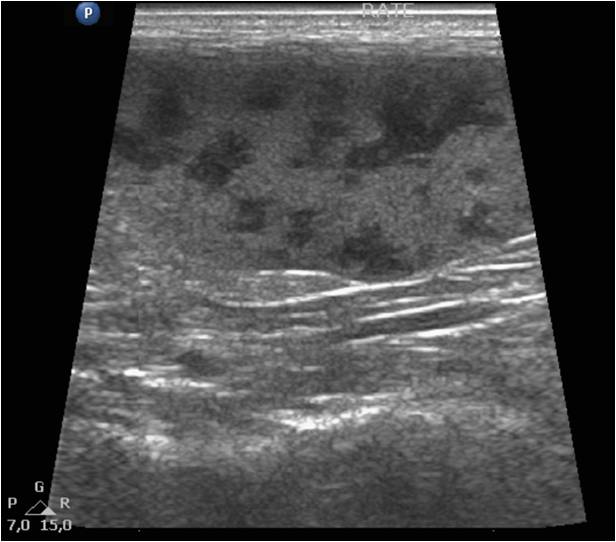

Le lymphome est une tumeur des cellules blanches sanguines particulièrement fréquente chez le furet. Le lymphome du furet peut affecter le système digestif, les noeuds lymphatiques, le foie, la peau voire les yeux ou le système nerveux. C'est une maladie dont la présentation est très variée. Le diagnostic réclame des examens d'imagerie (radiographie, échographie, scanner, ponction de moelle osseuse) couplé à des analyses en laboratoire spécialisé (cytologie ou histologie). Les examens sont importants à plus d'un titre, d'une part pour évaluer l'extension de la maladie et d'autre part pour confirmer la maladie. En effet de nombreuses autres maladies (coronavirus notamment) peuvent ressembler au lymphome chez le furet.

Maladie digestive du furet

Les furets sont très sujets aux maladies digestives. Leurs selles peuvent être de consistance plus ou moins moulées mais parfois on notera des diarrhées régulières. C'est ce que l'on appelle les maladies digestives chroniques du furet. Il existe de très nombreuses causes à cela, elles peuvent être d'origine alimentaire, inflammatoire, tumorale (lymphome), parasitaire ou encore bactérienne (hélicobacter). Le diagnostic se fait principalement par prise de sang, échographie et par endoscopie digestive. Cette dernière permet de faire des prélèvements pour confirmer le diagnostic et ajuster le traitement. La maladie digestive peut s'étendre au foie.